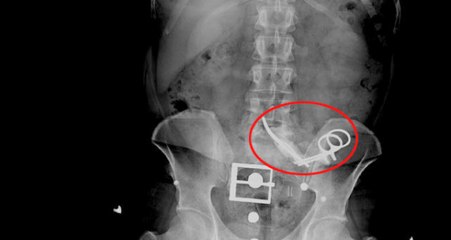

Aydın’ın Kuşadası ilçesinde mide rahatsızlığı nedeniyle özel bir hastanede operasyon geçiren 65 yaşındaki Nurcihan Öğmen’nin karnında makas unutuldu. Durumdan habersiz, iki ay boyunca karnında makasla yaşayan Öğmen, şiddetli ağrılar nedeniyle gittiği Söke Devlet Hastanesi’nde yapılan fark edildi. Öğmen’in karnındaki makas ameliyatla alındı.br br Evli ve sekiz çocuk annesi Nurcihan Öğmen, 5 Mart 2021’de Kuşadası’ndaki özel bir hastanede mide rahatsızlığı nedeniyle operasyon geçirdi. Hastaneden bir gün sonra taburcu edilen Öğmen’in ağrıları hiç dinmedi. Hareket etmekte güçlük çeken ve zamanla ağrıları daha da şiddetli hale gelen Öğmen, yaşadıklarını doktoruna aktardı.br br Doktorun kendisiyle ilgilenmediğini iddia eden Öğmen, ağrılarına dayanamayıp Söke’de başka bir doktora giderek muayene oldu. Burada yapılan kontrollerin ardından doktorun yönlendirmesiyle 3 Mayıs 2021’de Söke Devlet Hastanesi’ne başvurdu.br br Öğmen’in durumu, röntgen sonuçları ile netleşti. Karnında unutulan makas, iki ay sonra ameliyatla alındı.br br Nurcihan Öğmen, avukatı Mehmet Korkut aracılığıyla; mide operasyonunu yapan doktor ve hastane hakkında suç duyurusunda bulundu. Suç duyurusunda, “Bilinçli taksirle hayati tehlike yaratacak şekilde defalarca yaralama" suçunun işlendiği iddia edildi.br br “SEN NAZ YAPIYORSUN, AĞRILARIN GEÇECEK”br br Öğmen, ANKA Haber Ajansı’na yaptığı açıklamada, yapılan hata ve ilgisizlik nedeniyle büyük mağduriyet yaşadığını söyledi. Öğmen, “Ameliyattan sonra ağrılarım daha da arttı. O kadar şiddetli hale geldi ki neredeyse her hafta kontrole gittim. Doktor bana ‘sen naz yapıyorsun, ağrıların geçecek’ deyip, gönderdi. Her seferinde beni başından savdı, ilgilenmedi. Ne derdimi anlatabildim ne de acımı. Ben yaşadım başkaları yaşamasın. Çok canım yandı, çok mağdur oldum” dedi.br br “KİMSE BİZİ DİNLEMEDİ”br br Eşi Kudbettin Öğmen ise ameliyatın daha özenli yapılacağını düşünerek özel hastaneyi seçtiğini vurgulayarak, şunları söyledi:br br “Ameliyatın daha iyi yapılması için özel hastaneye gittik. Burada operasyon için 18 bin lira ödedim. Sonuç karnında makasla iki ay yaşadı. Sürekli gidip şikayetimizi dile getirdik, kulak asmadılar. Şimdi konuyu yargıya taşıdık, şu anda savcılığa dilekçeyi verdik, olay mahkemeye intikal etmiştir. Biz diyoruz ki kimse bu mağduriyeti yaşamasın. İki ay boyunca kimse bizi dinlemedi.